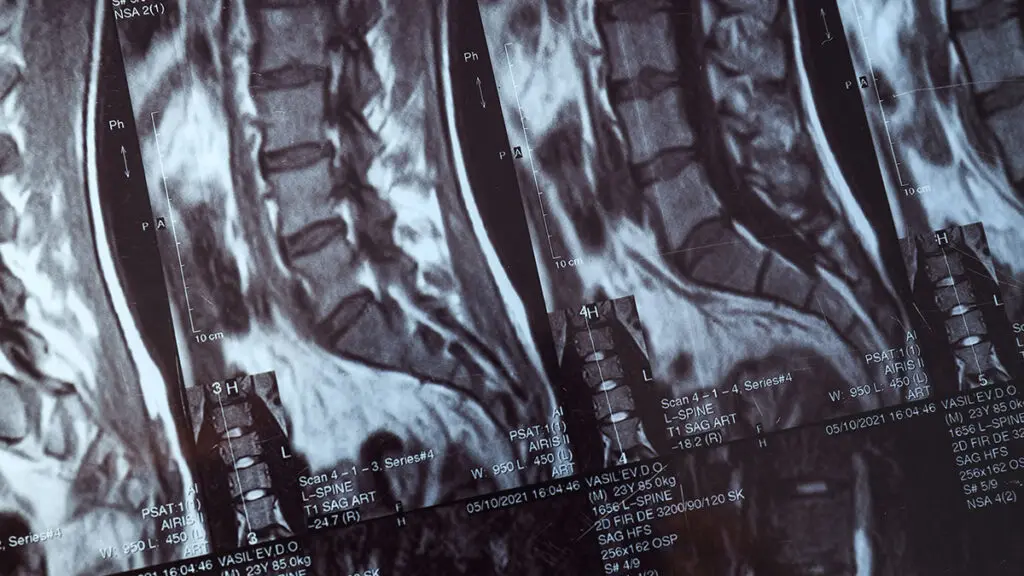

Global Spine Solutions offre a Roma approcci terapeutici avanzati e personalizzati per soluzione ernia del disco, con un team multidisciplinare che integra neurochirurgia vertebrale, terapia del dolore, fisioterapia e medicina rigenerativa. Ogni percorso terapeutico viene costruito su misura sulla base della diagnosi clinica e strumentale, privilegiando le soluzioni mininvasive prima di considerare l'opzione chirurgica.

Il percorso per soluzione ernia del disco disponibile presso Global Spine Solutions comprende: terapie farmacologiche mirate, infiltrazioni guidate (epidurali, periradicolari, faccette), radiofrequenza, nucleoplastica, terapie rigenerative (PRP, acido jaluronico) e programmi di fisioterapia post-procedurale. Il paziente viene seguito dall'inizio alla fine del trattamento con follow-up clinici periodici per monitorare i progressi.